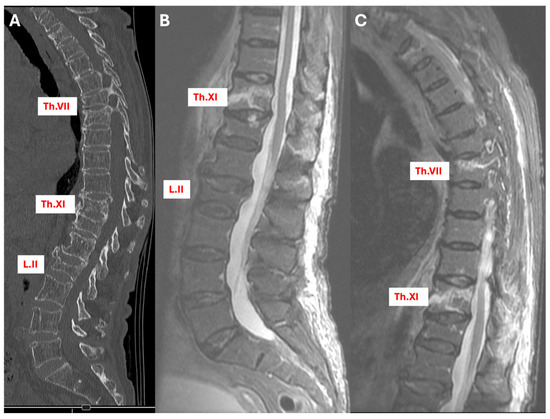

3.5.1. Case 1: Conservative Treatment Modification